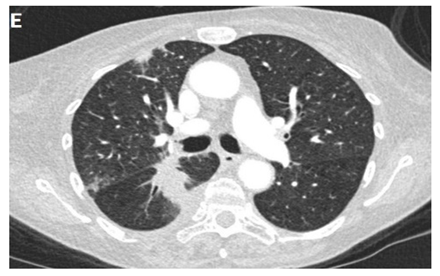

Even though X-ray is non-specific to pneumonitis, it is usually the first investigation performed. During the early phases, the most common finding on chest radiograph is perivascular haziness which frequently progresses to alveolar opacities [39]. Chest radiographs can show ground-glass opacity and/or consolidation in the radiation port. Consolidation usually has a nodular appearance but can be more confluent/lobar along with the irradiated port. Findings can be seen outside the radiation port as well. Some uncommon findings are ipsilateral pleural effusion with or without adjacent atelectasis [66]. Chest radiograph can also show bilateral interstitial infiltrates mimicking heart failure or acute respiratory distress syndrome (ARDS) [69,70]. All irradiated patients usually have some degree of abnormalities in the X-rays. Some fail to show any radiographic evidence of lung injury with pneumonitis. Early features exhibiting mild opacification of vascular markings are common, with later stages showing dense opacities. A radiographic straight-line effect may indicate the direction of the radiation port along the lines of pneumonitis [39,71] (Figure 1).

Figure 1.

Chest X-ray showing radiation pneumonitis Image 1—Frontal chest X-ray showing left upper lobe mass (arrow), the patient also had a right internal jugular port placed. Image 2—Post radiation treatment frontal chest X-ray showing increasing alveolar and interstitial opacities in the left upper lobe and in the left lower lobe in a patient suspected of radiation pneumonitis.

In the event of worsening symptoms after empirical antibiotics, Chest CT may provide more insights. Interestingly, the opacification lines in both X-ray and CT conform to radiation port rather than anatomical lines of lung structure, which could be diagnostic. Identified progression outside the lung field might suggest immune-mediated lymphocytic alveolitis [72]. Various stages of presentation provide different imaging outlooks (Table 3).

During the acute exudative stage, features of ground-glass attenuation or homogeneous consolidation may be noticed. A patchy consolidation that confirms the irradiation portal is also suggestive of the early phase. A discrete consolidation that conforms to the shape of the irradiation portal is proliferative changes of irradiation [71].

A chronic fibrosis stage with features of parenchymal distortion, traction bronchiectasis, and pleural thickening resulting in volume loss and irreversible changes are noticed. Refer to Table 2.